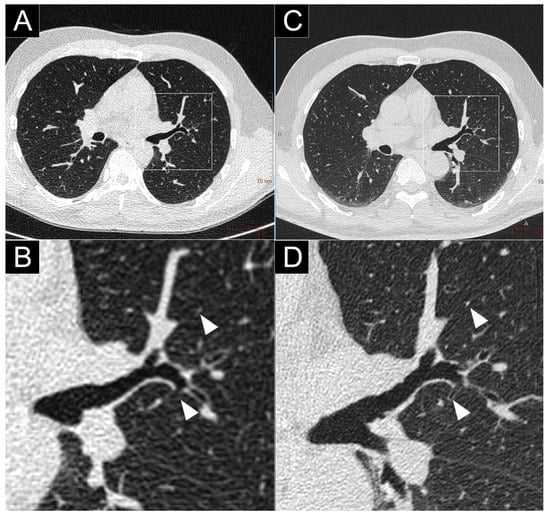

- Bartlett, D.J.; Koo, C.W.; Bartholmai, B.J.; Rajendran, K.; Weaver, J.M.; Halaweish, A.F.; Leng, S.; McCollough, C.H.; Fletcher, J.G. High-Resolution Chest Computed Tomography Imaging of the Lungs: Impact of 1024 matrix reconstruction and photon-counting detector computed tomography. Investig. Radiol. 2019, 54, 129–137. [Google Scholar] [CrossRef]